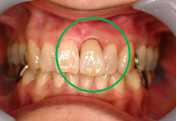

女性Mさん 50代(オールセラミック冠)

主訴

上の前歯をきれいにしたい。

治療内容

前歯3本にオールセラミック冠を被せて、歯並び及びすり減った歯を審美的に回復しました。歯ぎしりが強くあることがわかりましたので、マウスピースを使ってもらう事にしました。

所感

一番オススメな方法は、矯正をし、歯並びを整えた後、すり減って形が変わってしまった歯に被せ物をすることをお話ししました。患者さんは、3本に被せ物をすることにより歯並びをきれいにすることを希望されました。

治療後、「曲った前歯が長年コンプレックスでした。セラミックの歯の色合いや形が自然な仕上がりで、相談して本当に良かったです!神経を抜くこともなく治療ができ、予定よりも低料金にしてもらえたのがありがたかった。先生も、歯科衛生士さんも事務の人も皆、優しく寄り添った対応をしてくれました。ありがとうございました!」と、とても嬉しいお話しをしてくださいました。

オールセラミック冠3本:¥93,500(生活歯)×3本=¥280,500(税込)

Before

After